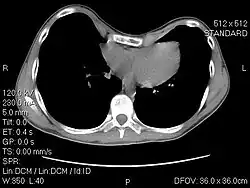

Klatka piersiowa lejkowata (łac. Pectus excavatum) – jedna z najczęstszych wrodzonych deformacji ściany klatki piersiowej. Polega ona na zapadnięciu się mostka na odcinku o różnej długości. Wada może być symetryczna lub asymetryczna. Często towarzyszy jej deformacja łuków żebrowych. Może współwystępować z innymi wadami postawy. Lejkowata klatka piersiowa może być jednym z objawów złożonych zespołów genetycznych np. zespół Marfana[1][2]. Wada może także powstać jako wynik innego procesu chorobowego tj. zaawansowanej krzywicy.